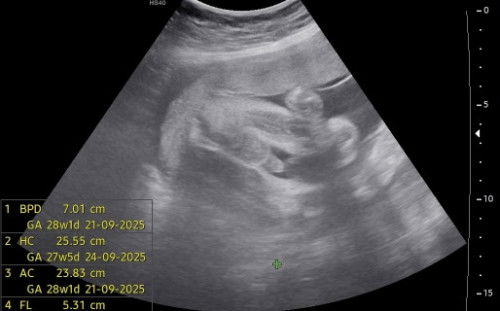

Hi mommy, kalau macam ni gender mmg confirm girl ke? Sebab doc kata suruh repeat scan dia sendiri was was . :(

Berapa weeks sis? Takpe, repeat je scan. Saya pun sono repeat scan. Buat detail scan masa 20 weeks nampak girl, tapi sono nak repeat juga masa 24 weeks untuk confirmation. And yes, baby girl.

Sy punya scan mcm ni baby girl... burger sign . Klau boy Sy scan 20w pun dah nampak pistol..

nmpk mcm burger tuh